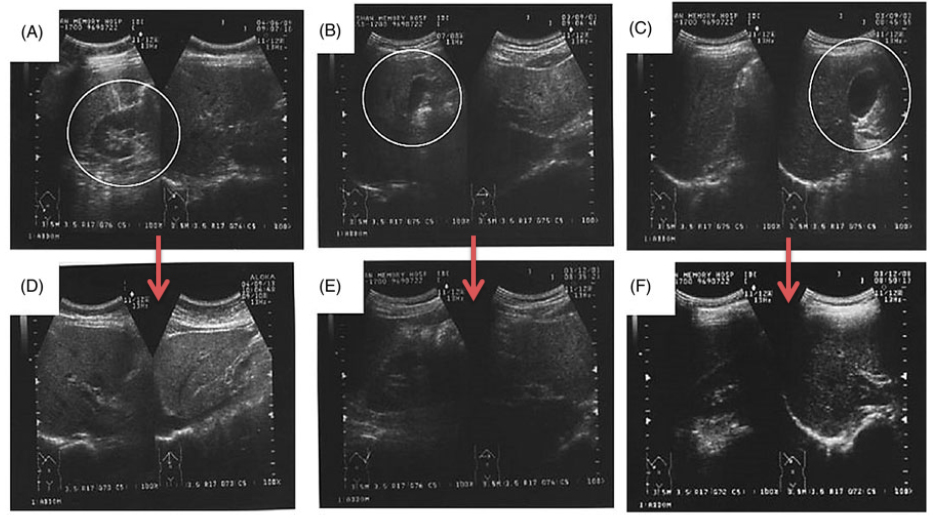

除此之外,灵芝还能使受试者的GOT与GPT平均值分别减少42%和27%。腹部超音波也显示,三位原本有初期脂肪肝或胆囊瘜肉的受试者,在经过灵芝调理之後,相关症状几乎都恢复正常(如下图)。

图(A)、图(B)、图(C)分别是第10、第19和第36号号受试者的腹部超音波照片,

前二者有轻微的脂肪肝,後者有胆囊瘜肉。吃了六个月的灵芝之後,

其腹部超音波的照片〔依序为图(D)、图(E)、图(F)〕,几乎看不到原先的症状。